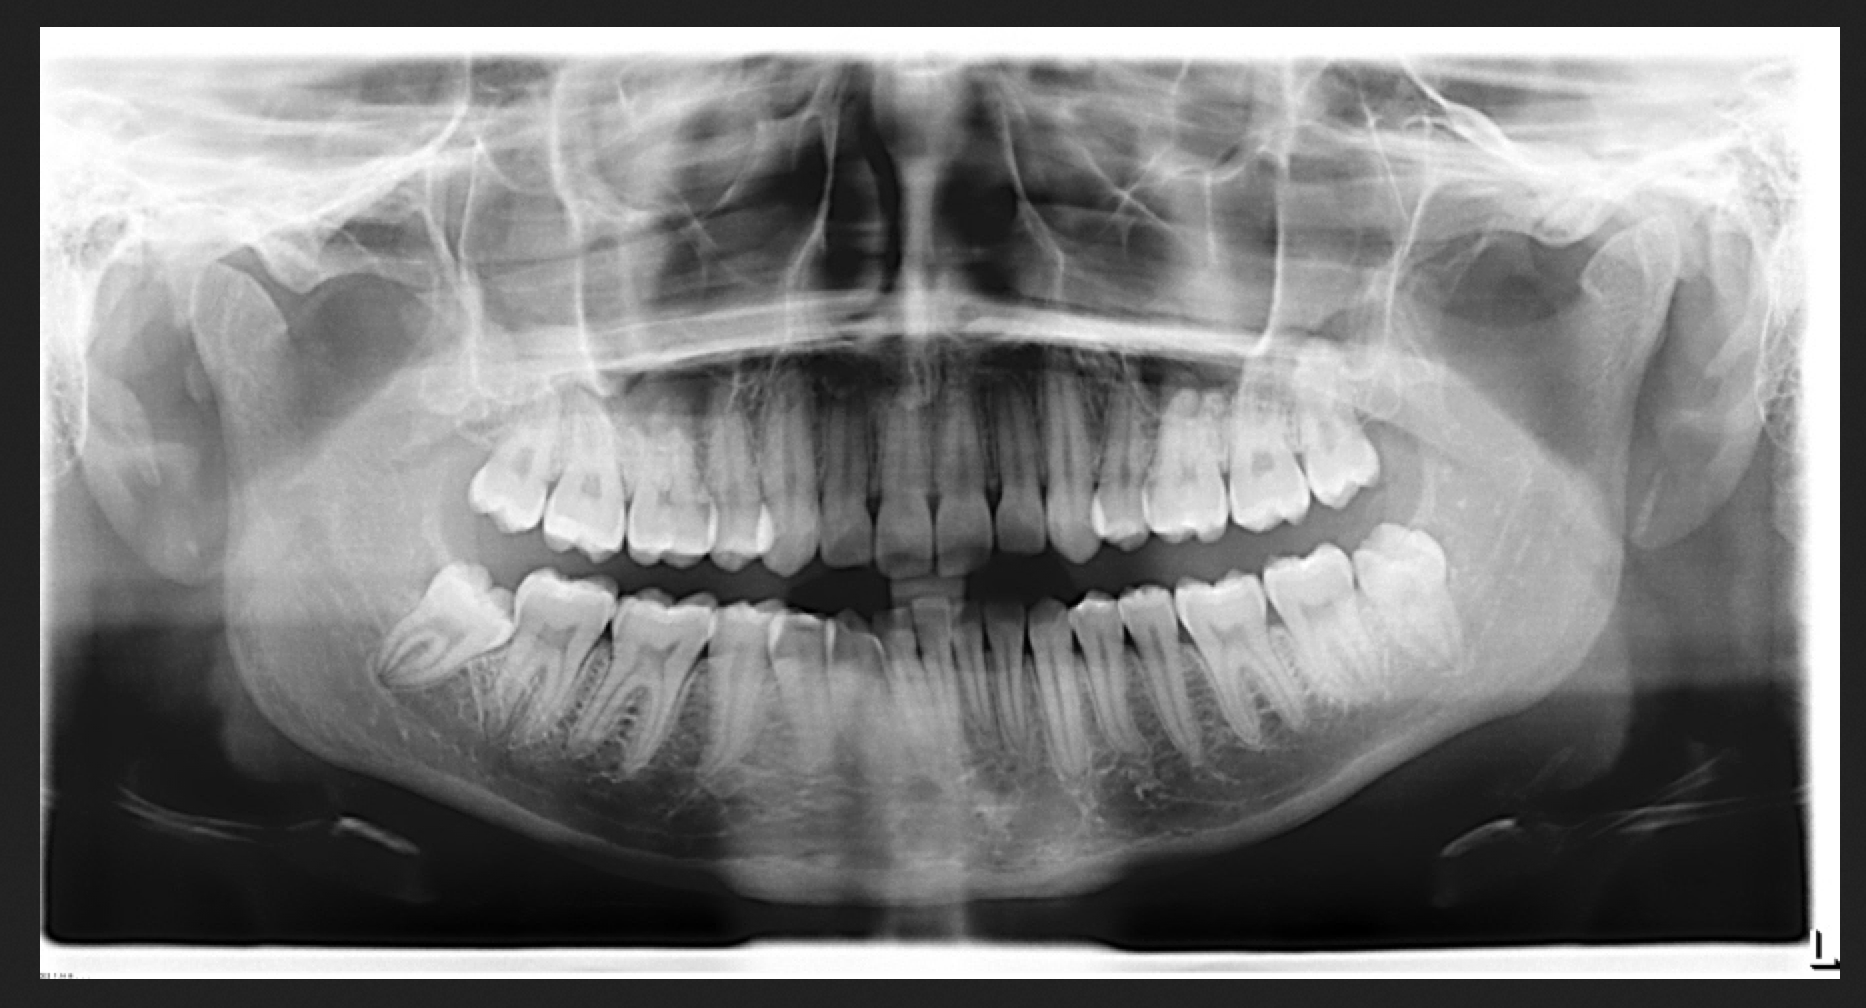

Panoramic xray image of teeth and mouth with wisdom teeth Parker Dental & Orthodontics Blog Wisdom Tooth X Ray Cost Philippines On average, the cost for wisdom tooth extraction can range from php 1000 to php 4,000 per tooth in the philippines. The average costs associated with wisdom tooth extraction can vary, providing a general overview of the rates, fees and expenses involved. This cost range can vary based on the treatment and the experience of. On average, you can expect. Wisdom Tooth X Ray Cost Philippines.

Orthopantomography, OPG Xray DR digital wisdom teeth. panoramic film x ray dental Stock Photo Wisdom Tooth X Ray Cost Philippines Average cost of wisdom tooth extraction in the philippines. In some cases, if the wisdom teeth are impacted or require oral surgery, the cost can. The average costs associated with wisdom tooth extraction can vary, providing a general overview of the rates, fees and expenses involved. This cost range can vary based on the treatment and the experience of. Average. Wisdom Tooth X Ray Cost Philippines.